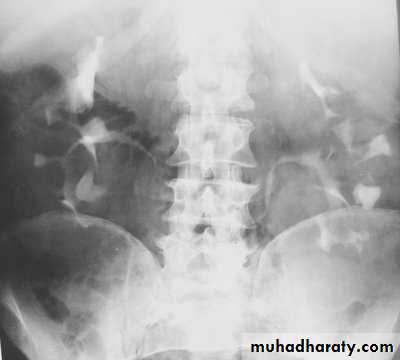

Horse shoe kidney -Kidneys may fail to separate.

-Almost invariably the lower poles remain fused.

-The kidneys axes are more parallel to the spine and malrotated.

-Diagnosis can be made by plain x-ray in some cases.

IVU shows

1. The kidneys at low position .

2.Close to the spine with long axis parallel to the spine .

3. Malrotation manifested by medially directed calyces.

4- The renal pelvis and ureters are anterior and lateral in position .